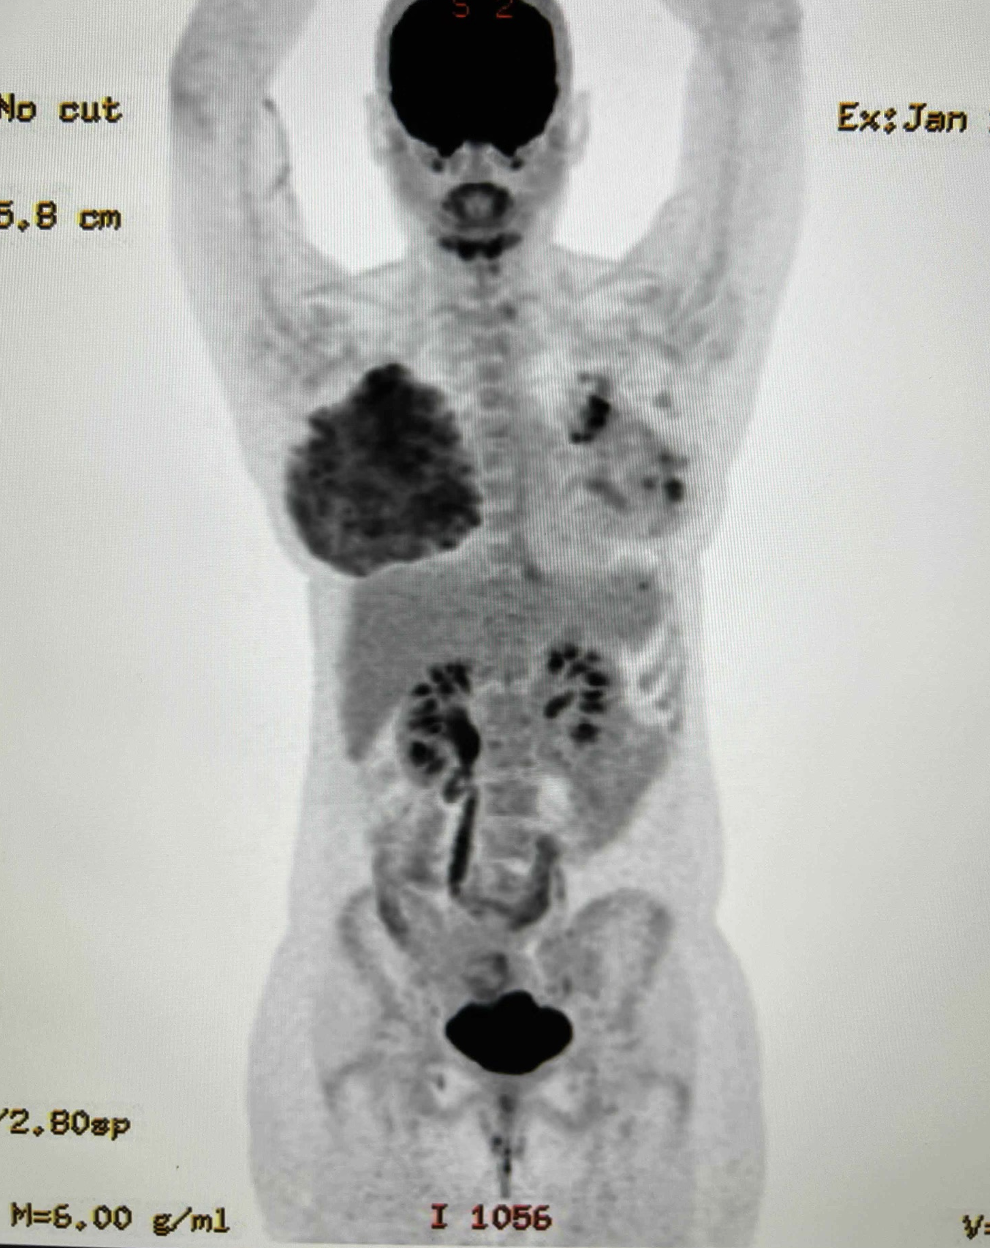

As an example of how extremely metabolically active the lactating breast is, a PET scan performed above for a left breast cancer (shown by the black areas in the left breast) demonstrates the remarkable lactating breast (right). This patient was mainly feeding on her right breast due to skin changes and inability to feed the infant on her left breast with cancer. You see that the lactating breast is actually MORE “FDG avid” (meaning it takes up more of the radio nucleotide, FDG, that the PET scan uses to determine metabolic activity) than the breast cancer itself!

The lactating breast is EXTREMELY active and powerful! THIS is why people can feel so bad with engorgement and inflammation. There is a LOT of blood flow and metabolic demand feeding the breasts during breastfeeding!